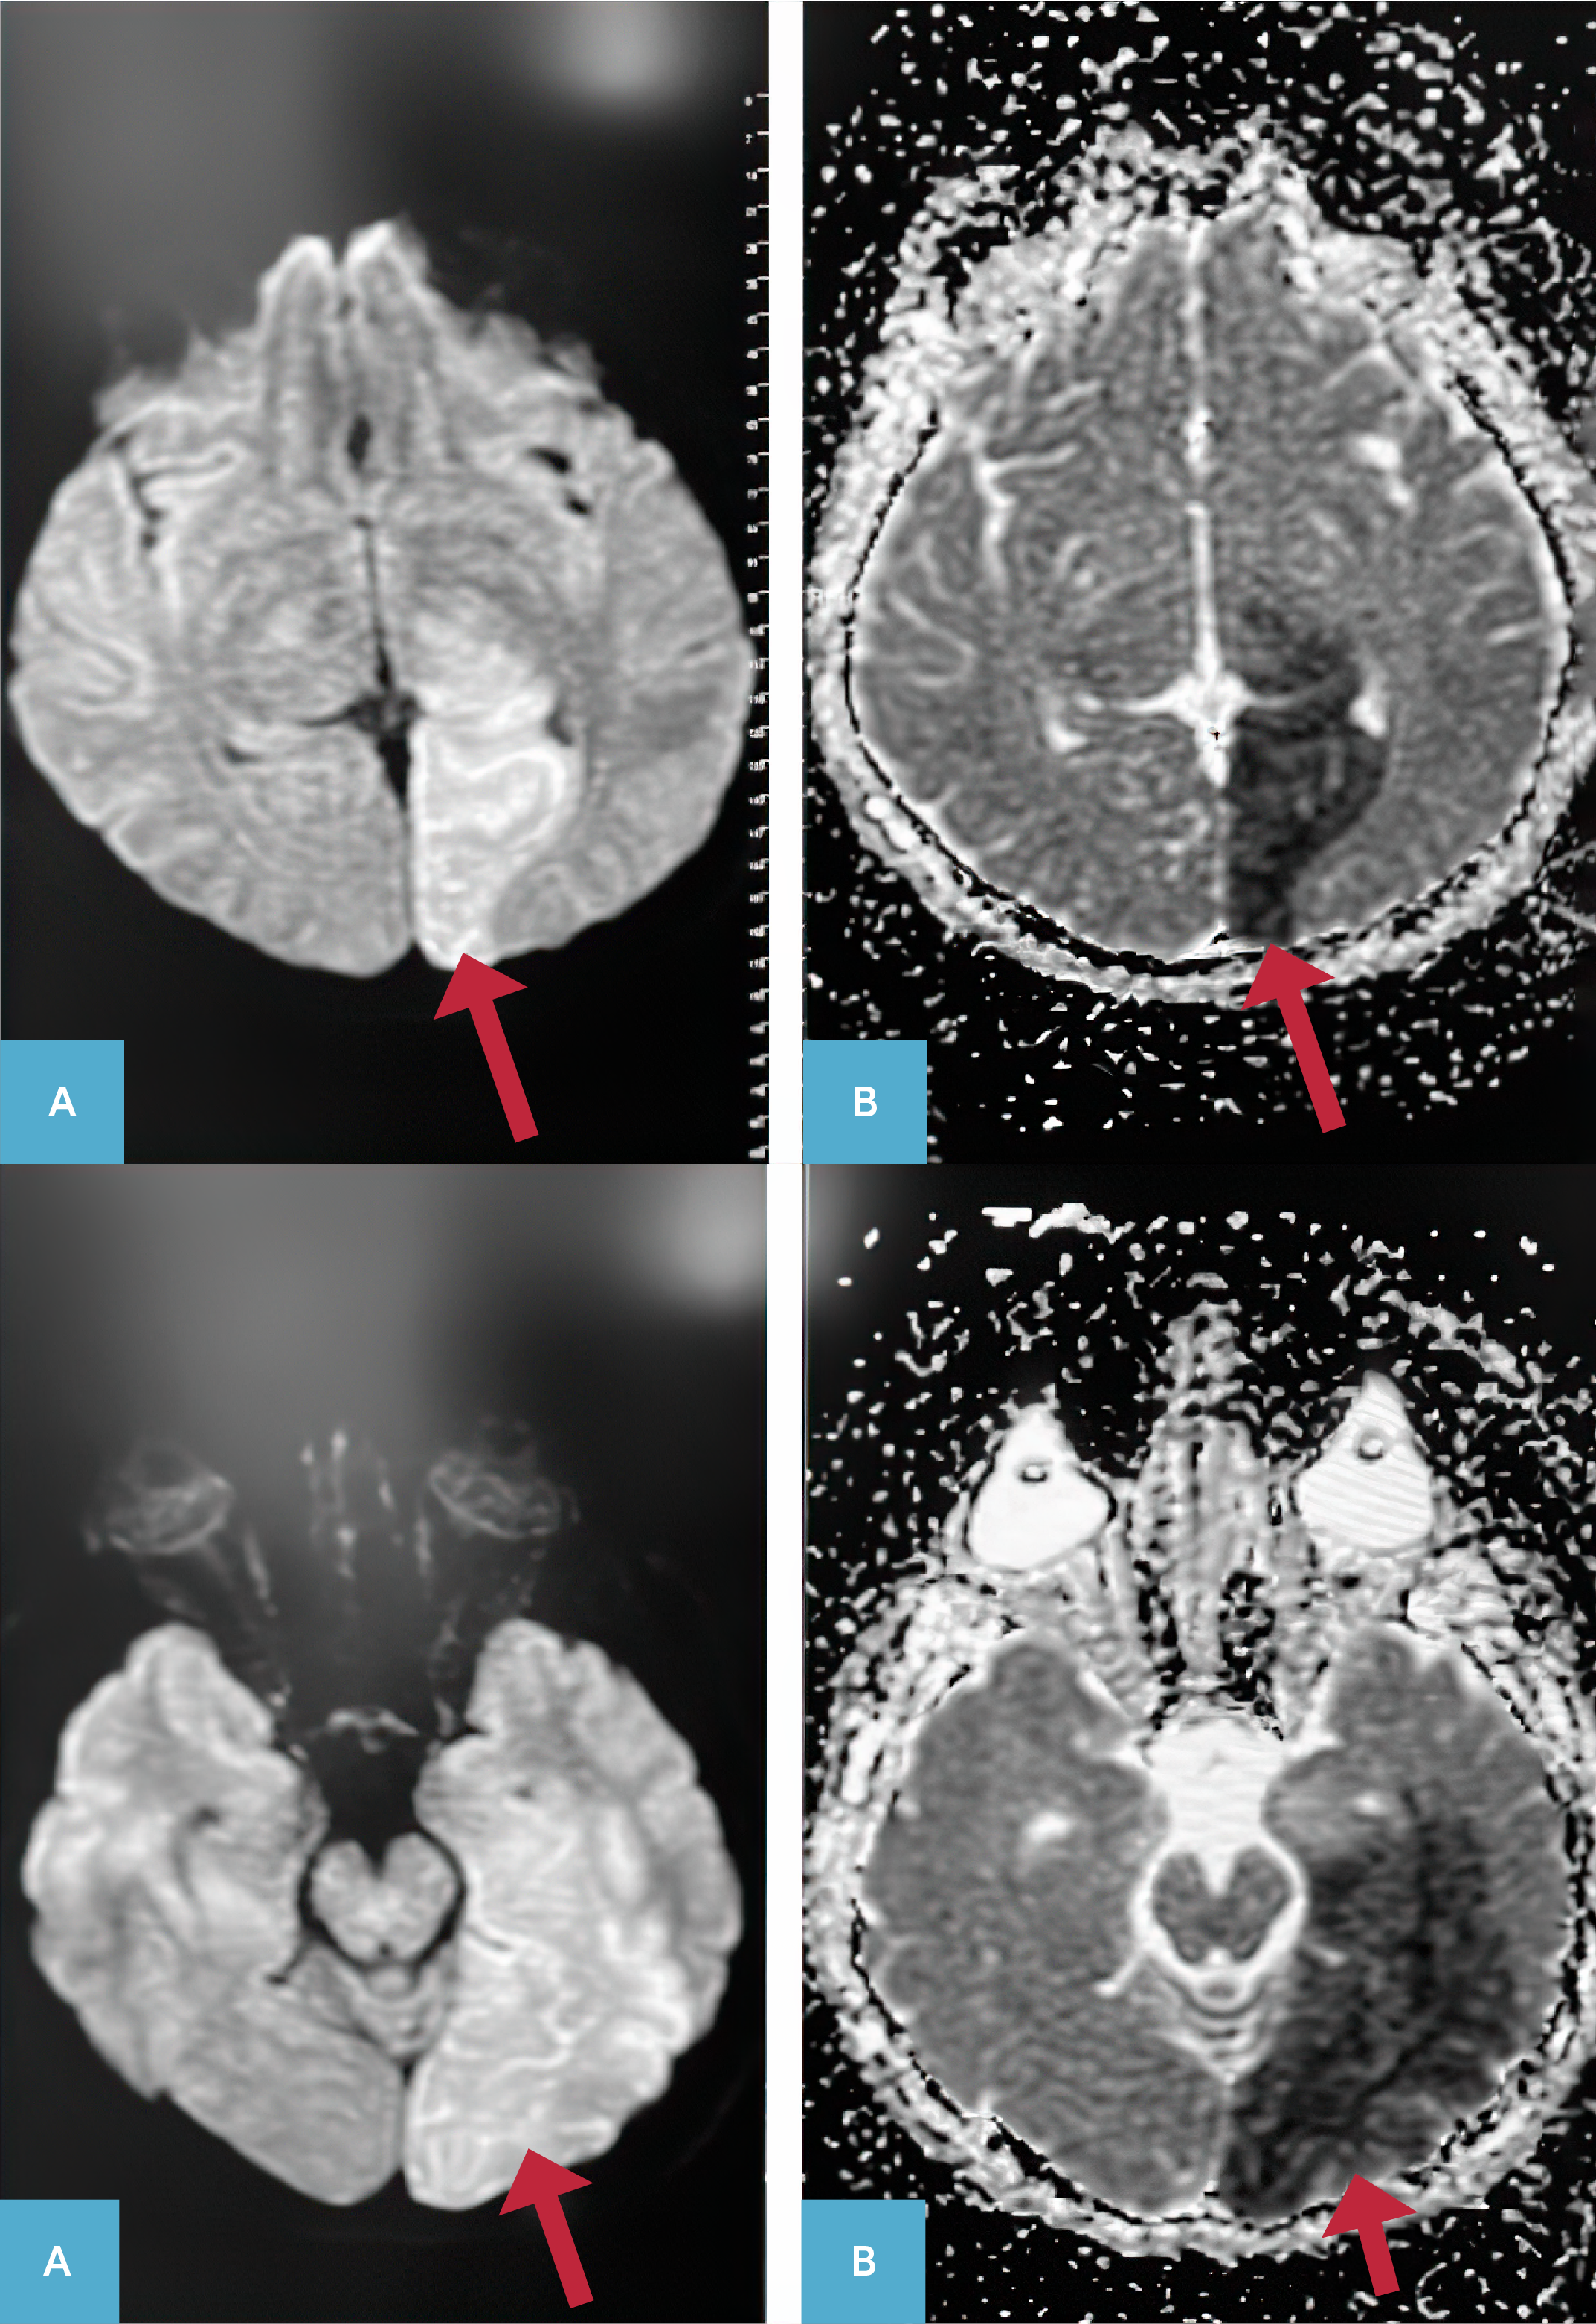

Resim 1.Serebral Difüzyon Manyetik Rezonans Görüntülemede Sol Posterior Serebral Arter Sulama Alanında Akut Enfarkt ile Uyumlu Difüzyon Kısıtlaması* A) Difüzyon ağırlıklı kesitler, B) Görünür difüzyon katsayısı ağırlıklı incelemeye ait kesitler. *Difüzyon kısıtlanmalarının olduğu lokalizasyonlar kırmızı oklarla gösterildi.

Kırk bir yaşındaki erkek hasta bilinç bulanıklığı, konuşmada bozulma, ateş yüksekliği ile acil servisimize başvurdu. Hastanın ateş yüksekliği ve halsizlik şikayetiyle tekrarlayan hastane başvuruları vardı ve şikayetlerine göğüs ağrısı eklenmesi nedeniyle üç gün önce başvurduğu dış merkezde akut koroner sendrom (AKS) tanısıyla anjiografi yapılmış, koroner stent takılmış ve sonrasında taburcu edilmişti. Kronik hastalığı ve düzenli kullandığı medikal tedavisi olmayan hastanın ilk değerlendirmesinde; vücut sıcaklığı 39.1°C, nabız sayısı 115/dakika (sinüs taşikardisi), solunum sayısı 22/dakika ve arteriyel kan basıncı 110/80 mmHg olarak tespit edildi. Genel durumu kötü, bilinç letarjik ve Glasgow koma skoru 12 idi. Oryantasyon ve kooperasyonu yoktu, ense sertliği mevcuttu. Kardiyak üfürüm duyulmadı. Hastanın kas gücü sağ üst ekstremitede 1/5, sağ altta 3/5, sol ekstremitelerdeyse 4/5’ti. Diğer sistemik muayeneler doğaldı. Lökosit sayısı 30 860/mm3, nötrofil sayısı 29 230/mm3, trombosit sayısı 289 000/mm3, alanin aminotransferaz (ALT) değeri 116 Ü/lt, aspartat aminotransferaz (AST) değeri 101 Ü/lt, üre düzeyi 49 mg/dl, kreatinin değeri 1.28 mg/dl, C-reaktif protein (CRP) değeri 128 mg/lt, prokalsitonin (PCT) değeri 46.48 ng/ml, arteryal kan laktat değeri 23.68 mg/dl idi. Tam idrar tetkikinde patoloji yoktu. Serebral bilgisayarlı tomografi (BT) ve toraks BT’de patoloji saptanmadı. Serebral difüzyon manyetik rezonans görüntülemede, sol posterior serebral arter (PCA) sulama alanına uyan lokalizasyonda akut enfarkt alanı mevcuttu (Şekil 1).